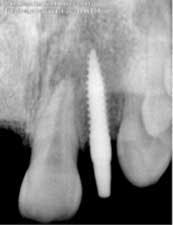

Fig. 2: Implant placement — 3.0 x 14 mm implant placed on No. 10.

Fig. 3: Implant temporization No. 8 and No. 10 — 3.7 mm x 13 mm implant placed on No. 8.Patient returned one month later after returning from a cruise, complaining that her “implants felt loose.” She was very honest and admitted to not taking the antibiotics and not following any dietary restrictions while on vacation, because “they felt so strong.” Periapicals taken that day showed a catastrophic failure, with large areas of bone loss surrounding both implants (Fig. 4).